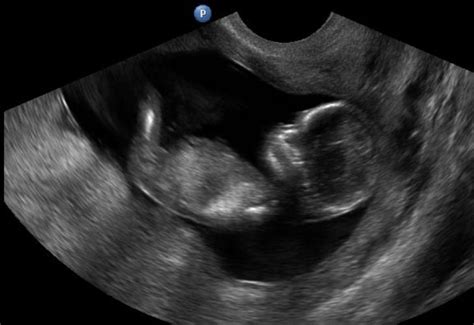

A terhesség korai szakaszában a méhen belül beágyazódott pete körül kialakuló felritkulás, illetve folyadék-felszaporodás látható. A méh ultrahangképén kerek fekete folt jelenik meg, mintha lyukasztóval ütötték volna azt át. A kör alakú folt két legtávolabbi pontjának távolságát mérjük, ami megadja a petezsákátmérőt.

A petezsákot a terhesség korai szakaszában mérik. Körülveszi az embriót és a magzatvizet is. A petezsák a magzat táplálását és fejlődését segíti. Az ultrahangos vizsgálat során a petezsák meglétét keresik a terhesség nagyon korai szakaszában, ez mutatja meg, hogy a teherbeesés megtörtént. Általában már az ötödik hét körül látható a petezsák.

Ha az orvos vagy a szonográfus látja a petezsák jelenlétét, az nagyon jó jel. Az ultrahangos vizsgálat során az orvos látja, hogy van-e valamilyen probléma a petezsákkal: lehet kóros az alakja, lehet, hogy nem úgy növekszik, ahogy kellene, és az is lehet, hogy üres, még akkor is, amikor a szikhólyagnak már látszódnia kéne benne. Ennek általában a hatodik hét körül már láthatóvá kell válnia.

A petezsákban látható szikhólyagnak nagyon fontos szerepe van, hiszen ez táplálja az embriót addig, amíg kialakul a keringési rendszere. Üres petezsákról akkor beszélünk, ha nem található benne a szikhólyag: azaz a megtermékenyített petesejt megtapad a méhfalon, de nem fejlődik tovább. Az első trimeszterben bekövetkező vetélések felét az üres petezsák teszi ki. Oka egyelőre nem tisztázott, de valószínűsítik, hogy kromoszóma-rendellenesség áll a háttérben. Az a feltételezés, hogy a test felismeri, hogy kóros a terhesség és nem folytatódik a folyamat.